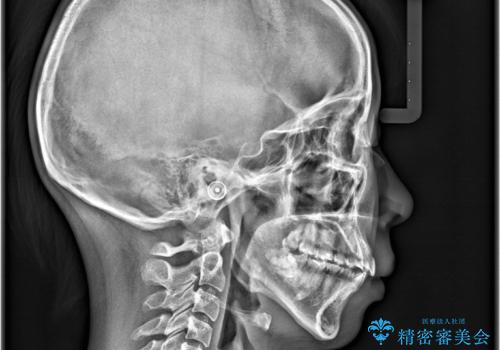

- 「歯の捻じれとがたつき」を主訴に来院された患者様です。

軽度な捻転と叢生だったため、インビザラインのモデレートで治療を行いわずか半年で治療を終える事が出来ました!